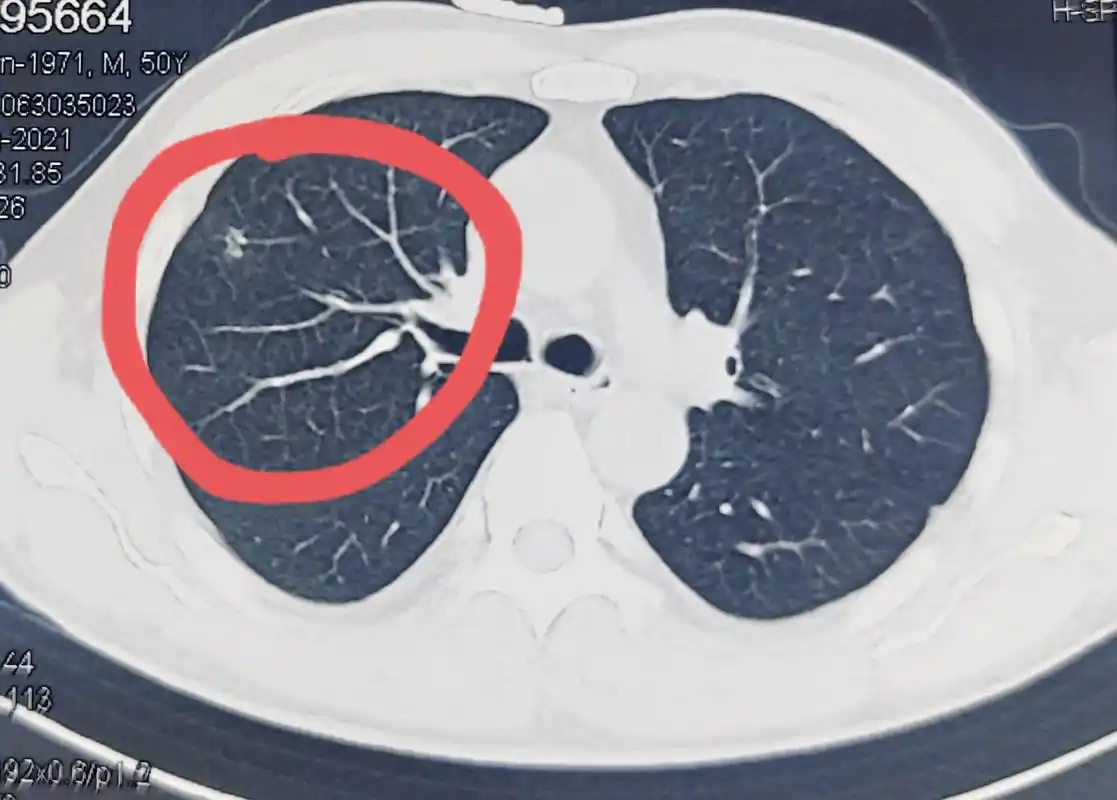

如此早期的肺结节你能发现吗

肺结节是不是肺癌?"血管征"是重要的鉴别要点!

肺结节(图片来自网络)